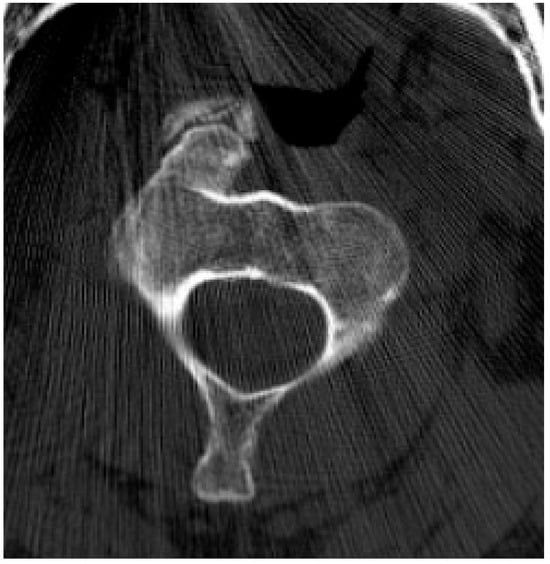

2.2.1. Osteochondroma

- Sinelnikov, A.; Kale, H. Osteochondromas of the Spine. Clin. Radiol. 2014, 69, e584–e590. [Google Scholar] [CrossRef] [PubMed]

- Rajakulasingam, R.; Murphy, J.; Botchu, R.; James, S.L. Osteochondromas of the Cervical Spine: Case Series and Review. J. Clin. Orthop. Trauma 2020, 11, 905–909. [Google Scholar] [CrossRef]

- Yakkanti, R.; Onyekwelu, I.; Carreon, L.Y.; Dimar, J.R. Solitary Osteochondroma of the Spine-A Case Series: Review of Solitary Osteochondroma with Myelopathic Symptoms. Global Spine J. 2018, 8, 323–339. [Google Scholar] [CrossRef]